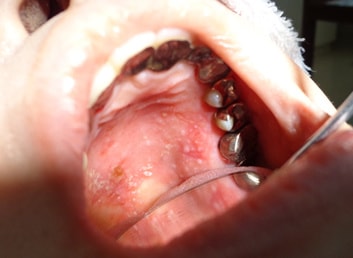

先日、上あごの歯ぐきの痛みを訴えてこられた方ですが、写真のように粘膜の剥離、潰瘍で傷だらけとなり、お口の中も汚れている状態でした。

状況をご説明し、口腔内清掃を行い、ご自宅でも清掃に気を使っていただくようにしたところ、1週間後にはほぼ完治してしまいました。

このように、コロナ禍とはいえ気になることがあった場合にはお近くの歯科医院へ受診されることをお勧めします。